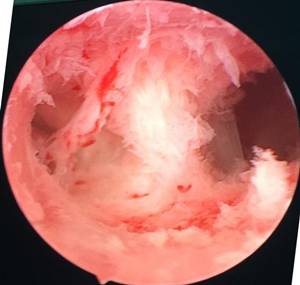

医生用来破解宫腔粘连的*器武**是“宫腔镜”。宫腔镜可以直接观察到宫腔内的情况,包括土壤的情况,宫腔容积的情况,溶洞形成的情况。可以借助专业的工具来破除这些形成的粘连带,打通各个孔道,恢复宫腔正常形态。

(图:宫腔镜下所见宫腔粘连)